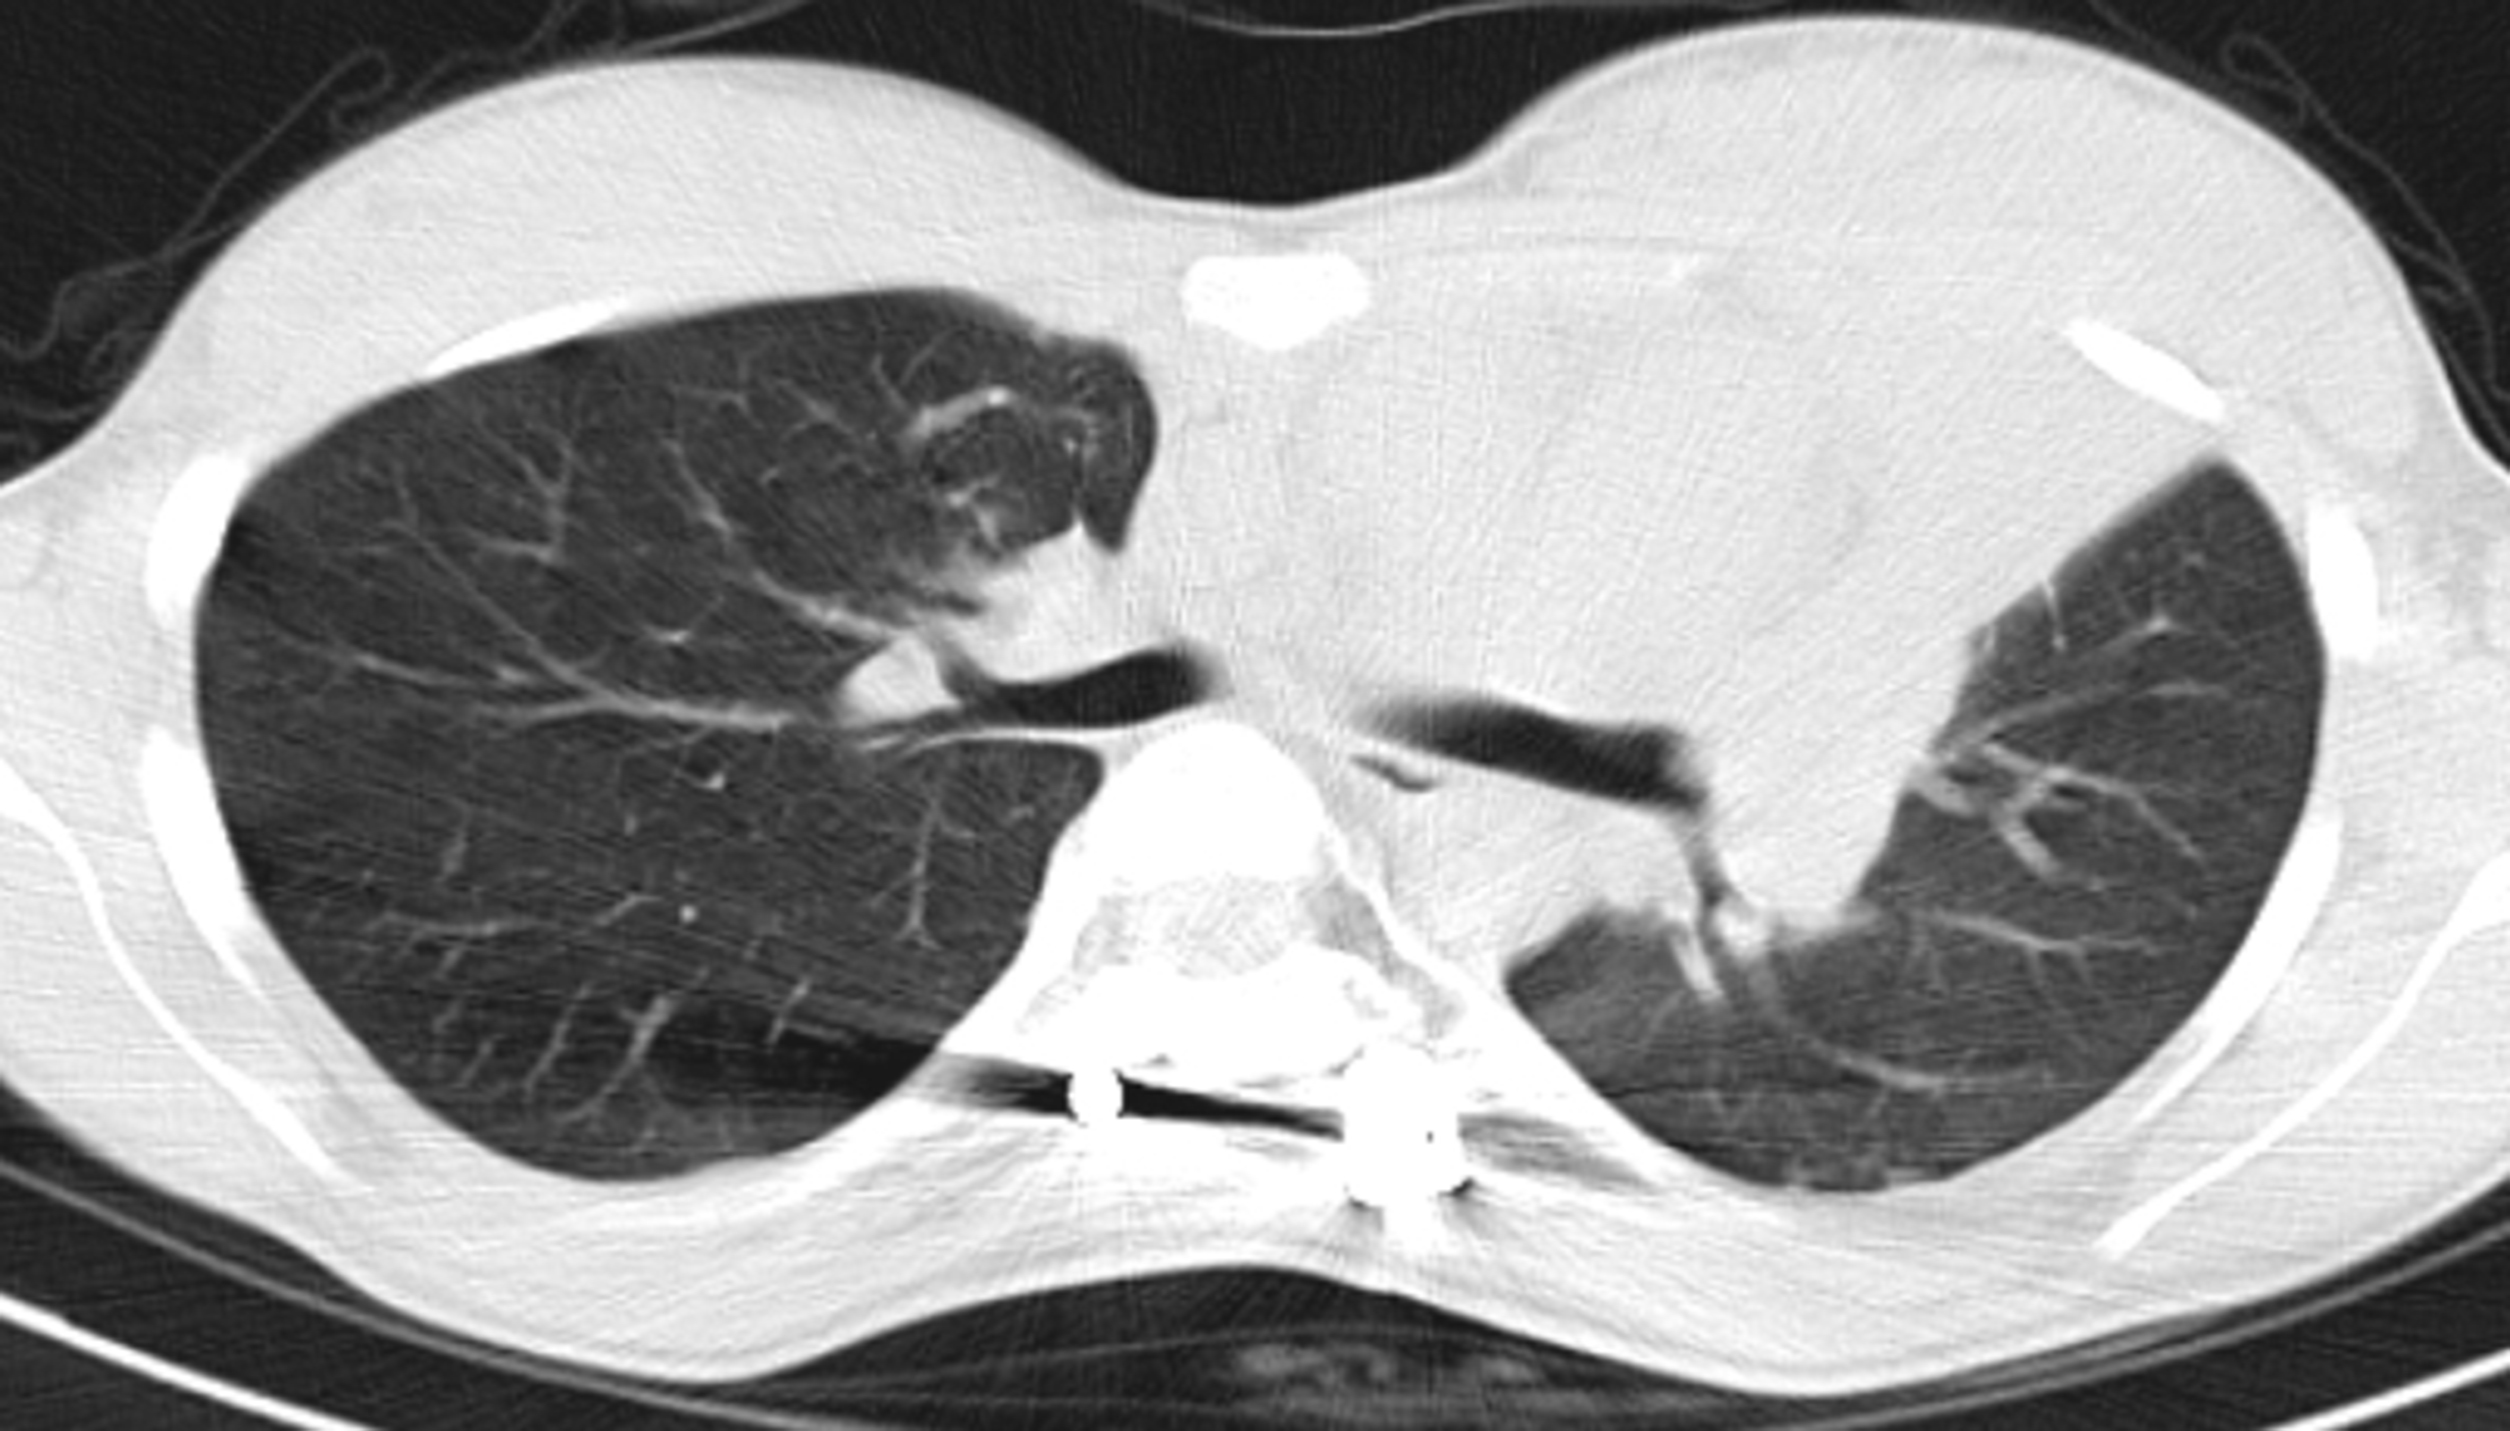

- Figura 3 (Português (Portugal))